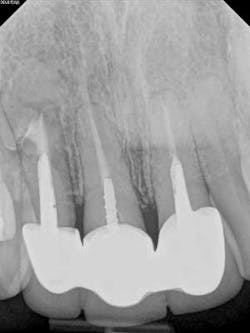

A 52-year-old male patient presented to the office with pain related to tooth No. 9. After radiographic review (figure 4), it was noted that No. 9 had previous endodontic therapy along with a large cast post. The patient was happy with the esthetics of the crown on No. 9, and the clinical and radiographic review showed intact margins and a sound restoration. The recommendation was made to take a narrow-field CBCT image of tooth No. 9. It revealed periapical pathology related to tooth No. 9 that had not broken through the buccal or palatal cortex (figure 5). No fractures were noted and disassembly of the current restoration was not ideal due to the size of the casting in place. The patient was appointed for microsurgical endodontic treatment to save tooth No. 9.

Again, a very minimal osteotomy could be made with the use of an operating microscope. After proper root resection, root-end prep, the placement of a biocompatible bioceramic filling (figure 6), the site is ready to be grafted. The lesion is removed and sent for biopsy, and we are left with a zero-degree bevel to root-end prep, and filling at this point becomes analogous to a Class I restoration. After radiographic verification that we have proper root resection and adequate apical fill, our bone grafting material was placed and final radiographs where taken (figure 7).